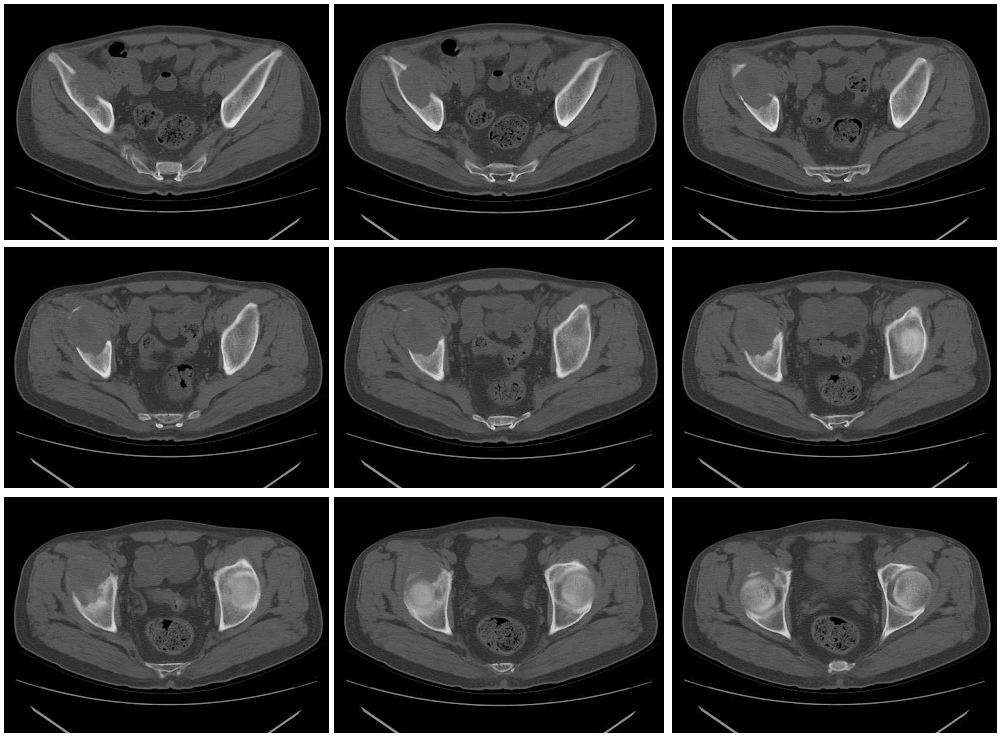

男性,57岁,右髋部疼痛一月

骨质破坏严重,考虑恶性肿瘤。

溶骨性破坏,并软组织肿块,恶性肿瘤,转移瘤可能性大。

右髂骨中心性溶骨性膨胀破坏,但边界尚清,不排外良性可能

右侧髂骨溶骨性骨质破坏,且见有软组织肿块,首选考虑转移瘤,其次考虑淋巴瘤或骨肉瘤。